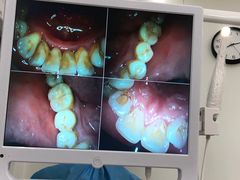

• -牙博士口腔品牌连锁(杨浦店)

开心么么豆 | 21-02-01

报错